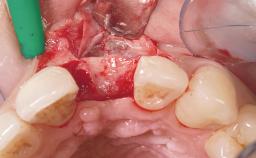

Late Placement of an Implant in a Maxillary Left Central Incisor Site

A 36-year-old female patient was referred for the replacement of the upper left central incisor (tooth 21), which had fractured. Although the tooth had been asymptomatic for many years, the crown began to loosen, at which time she presented to her dentist for an assessment. Teeth 21 and 22 had both been endodontically treated many years previously. She was a healthy individual and a non-smoker.

Soft Tissue Grafting Simultaneous

Soft Tissue Contour and Volume Slightly compromised